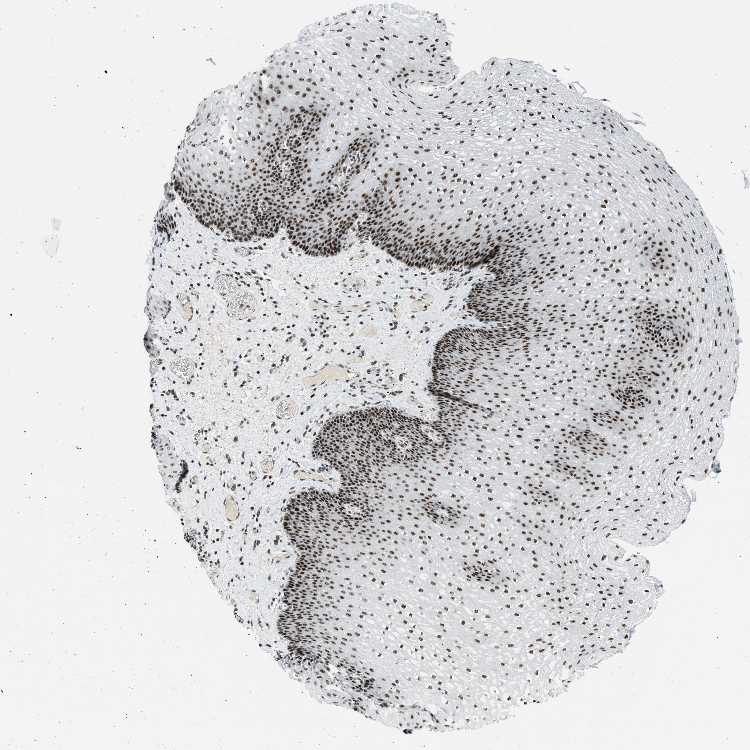

ESOPHAGUS - Antibody stainingi

Antibody staining in the annotated cell types in the current human tissue is reported as not detected, low, medium, or high, based on conventional immunohistochemistry profiling in selected tissues. This score is based on the combination of the staining intensity and fraction of stained cells.

Each image is clickable and will lead to virtual microscopy that enables deeper exploration of all samples and also displays staining intensity scores, fraction scores and subcellular localization as well as patient and tissue information for each sample.

Antibody HPA018334

Squamous epithelial cells High